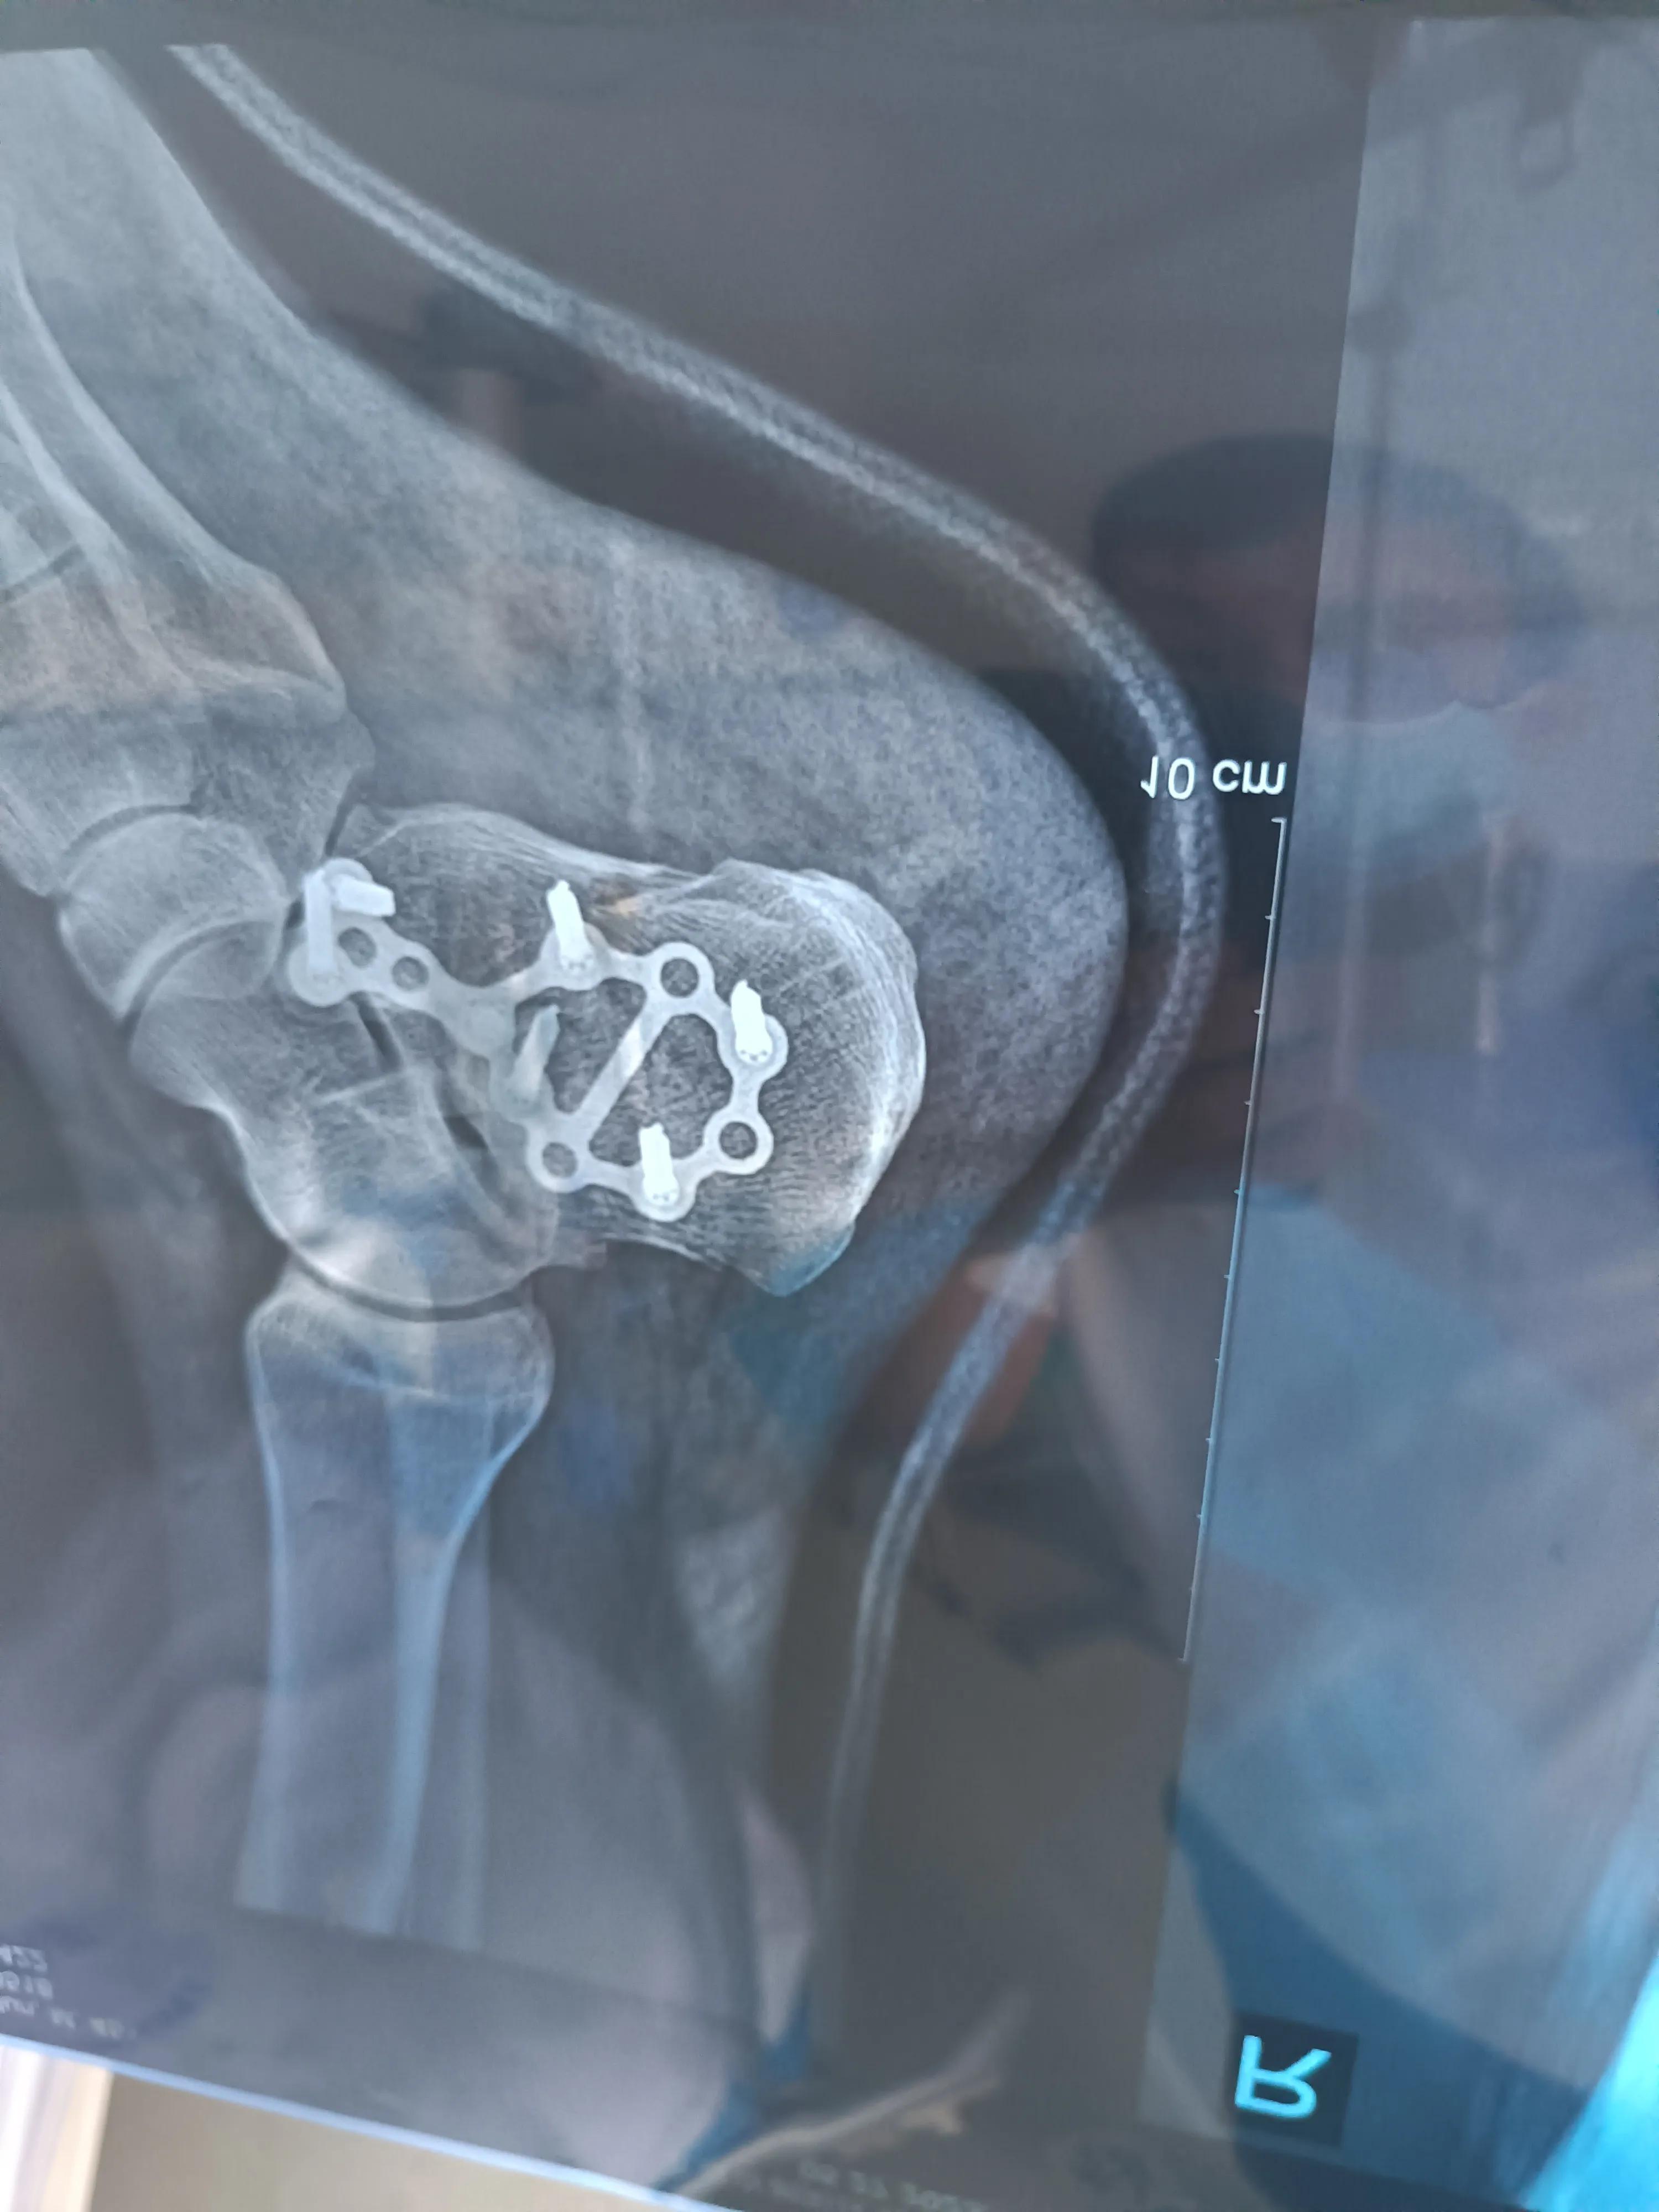

这位大哥是在装卸货物时受的伤,属于 跟骨粉碎性骨折,也做了手术,手术中加了钢板和6颗钉子, 脚后跟粉碎性骨折一般可定为8级、9级、10级伤残。

脚后跟粉碎性骨折为较严重的骨折,一般会残留局部的改变,可鉴定为10级伤残。如果跟骨骨折治疗后有残余疼痛、行走疼痛和跟变形的情况,可鉴定为9级伤残。如果骨折残留有明显的功能障碍,无法行走或影响日常生活和工作,可根据情况确定为8级残疾。

具体伤残等级的评定,应根据骨折程度、恢复情况、后遗症的有无来进行综合判断,医院开具相关证明后由伤残鉴定中心判定。

在实践中因为一般像遇见跟骨骨折的很少,一般都是内外环呀,或者双环呀,或者多环呀,单纯跟骨骨折,现在评残标准其实是有点儿难度的。伤残鉴定基本上是针对患者的外伤,在一系列系统治疗病情稳定不再产生变化后,对遗留的功能障碍和肢体不全进行评估,从而评定伤残等级。